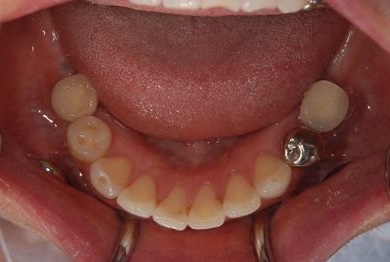

インプラントの症例写真 IMPLANT

インプラント治療+セラミック治療

| 治療内容 | インプラント2本、メタルボンドセラミッククラウン4本、ジルコニアフレームオールセラミッククラウン1本(オールセラミック用土台1本) | ||||||||||||||||||||||||||||||||